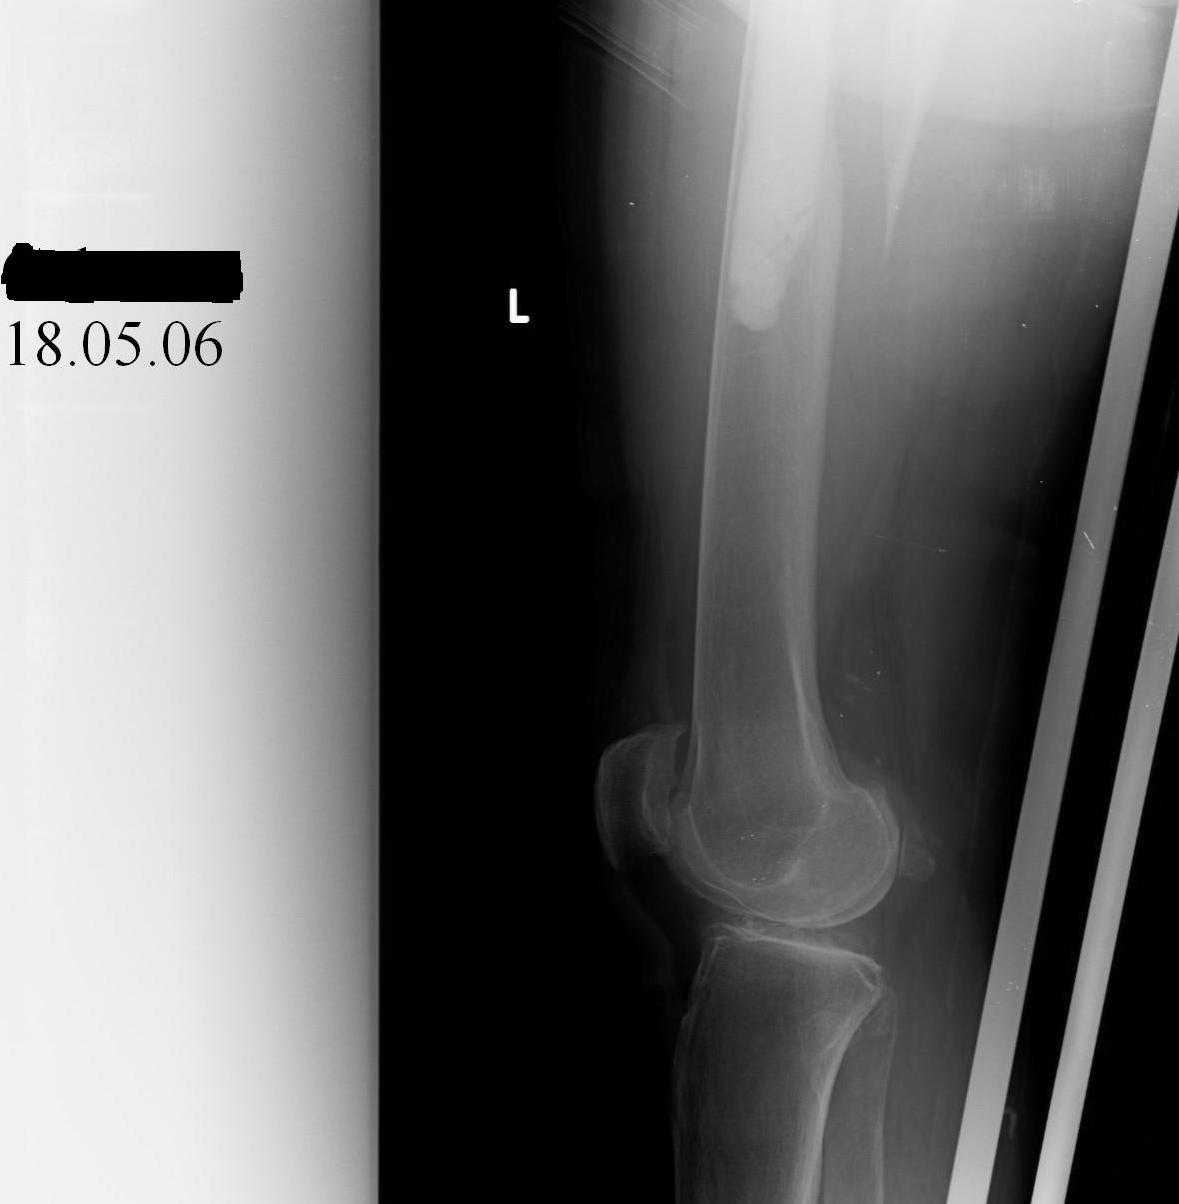

Re: Перипротезный перелом

Hello! This is just illustration in one of the choice of treatment